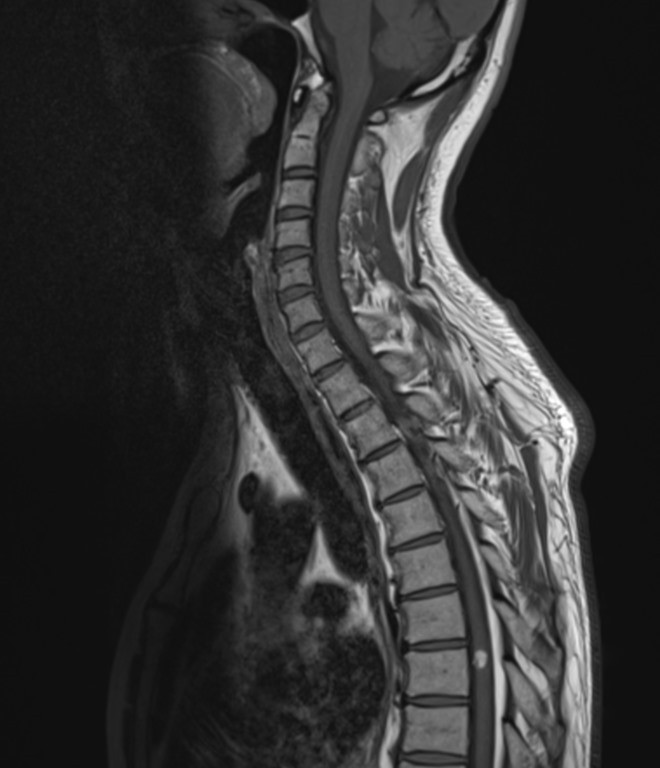

Resonancia Magnética de Columna

Envíado por Dr. José Rafael Chang Calero